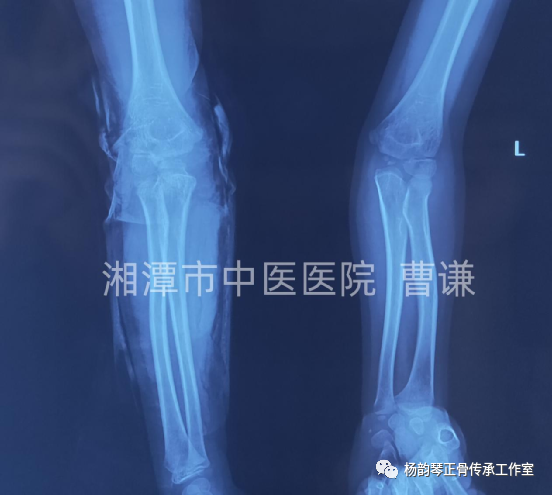

伤后半月余复查骨折对位对线良好,肱桡关节匹配良好,改直角托板固定,每次换药进行被动肘关节屈伸锻炼,这样有利于促进关节功能早期恢复。

伤后近一月拍片复查骨折愈合良好,肱桡关节匹配正常。